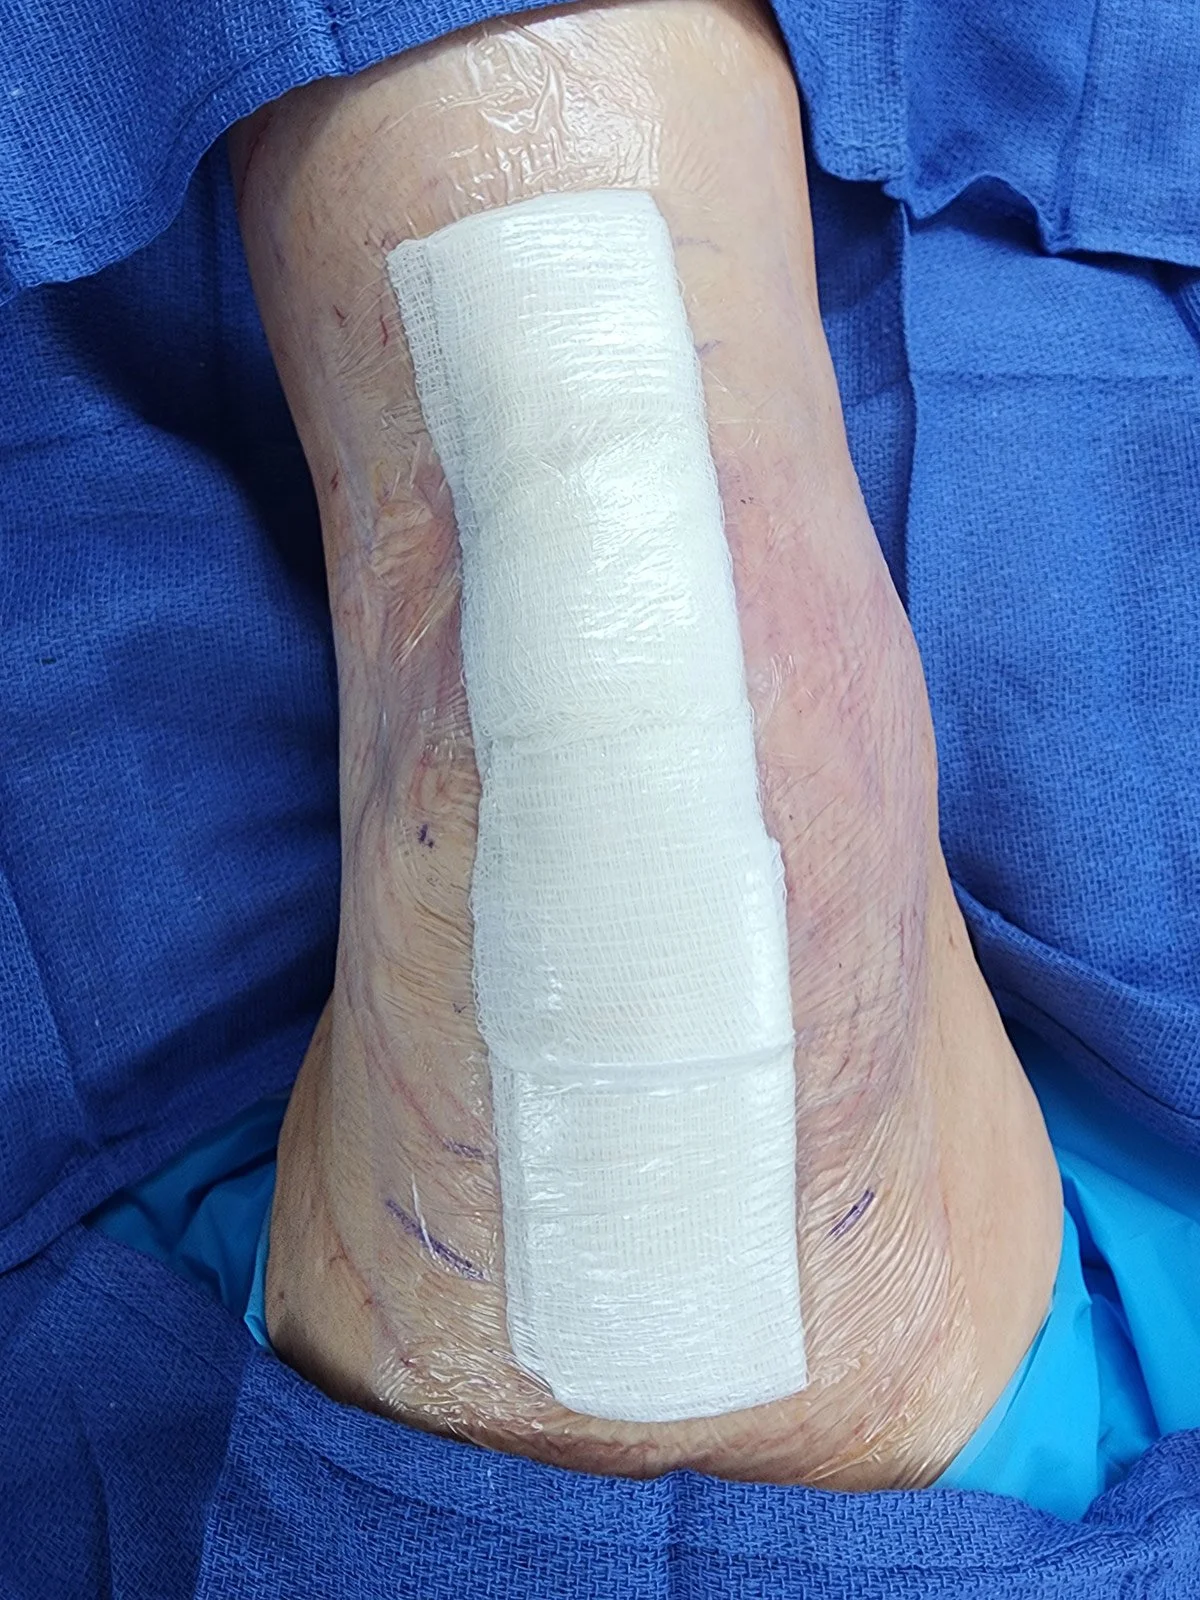

Dressings

Your wound will be covered with a waterproof dressing.

It is ok to shower after surgery. It is important to keep your dressing on, do not remove the dressing. It will be removed for you at your first postoperative visit.